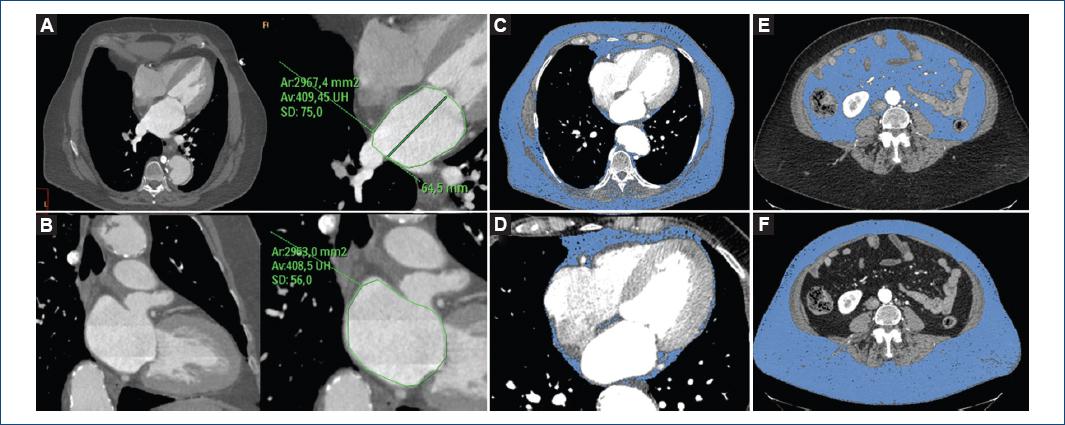

Para evaluar las dimensiones auriculares se realizaron mediciones en las vistas de dos y cuatro cámaras, obtenidas mediante ajuste de reconstrucciones multiplanares. Se determinó por planimetría manual el área máxima (sistólica) de la AI en ambas vistas y la longitud anteroposterior en la vista de cuatro cámaras (Fig. 1). De este modo se calculó el volumen auricular mediante la técnica biplanar de área/longitud basada en siguiente formula (0.85 x Área 4c x Área 2c/Longitud eje perpendicular desde el anillo mitral hasta la pared posterior de la AI). Tanto la orejuela izquierda como los ostium de las venas pulmonares fueron excluidos del análisis22,23. Las medidas fueron posteriormente indexadas a la superficie corporal (Dubois&Dubois).

Figura 1 Mujer de 70 años, con hipertensión y tabaquismo como factores de riesgo coronario, e IMC de 33 kg/m2. Evaluación de las dimensiones de la aurícula izquierda en vistas de cuatro cámaras (A) y dos cámaras (B) mediante reconstrucciones multiplanares obtenidas en la fase del 40% del ciclo cardíaco. En las vistas axiales (C, E y F) se observan las determinaciones de la grasa corporal total (C), visceral (D) y subcutánea (E) resaltando solo el tejido con una densidad de entre —190 y —30 unidades Hounsfield. En el panel D se presenta una vista de cuatro cámaras con el volumen de grasa pericárdica. Grasa corporal total: 10,682 cm3/m2; grasa torácica: 3,047 cm3/m2; grasa pericárdica: 104 cm3/m2 (3.4%); grasa abdominal: 7,634 cm3/m2; grasa visceral: 2,148 cm3/m2 (28% de la grasa abdominal); grasa subcutánea: 5,486 cm3/m2 (72% de la grasa abdominal); espesor de grasa subcutánea: 110.4 mm; circunferencia abdominal: 118.6 cm.

El volumen total de grasa corporal se evaluó desde el opérculo torácico hasta la región craneal de las cabezas femorales utilizando una técnica de reproducción de volumen y todas las mediciones se indexaron a la superficie corporal (cm3/m2). Para las mediciones del volumen de grasa se verificó la exactitud de todos los tejidos detectados automáticamente y se realizaron ajustes de forma manual y secuencial en vistas sagital, coronal, axial y utilizando el revestimiento de grasa tridimensional (Fig. 1). El volumen de grasa visceral se definió como la grasa incluida en la cavidad visceral, mientras que el volumen de grasa subcutánea abdominal se definió como el volumen de grasa abdominal menos el visceral (Fig. 1). El volumen de grasa pericárdico se evaluó desde 15 mm por encima del borde craneal del tronco coronario izquierdo hasta el diafragma. La pared torácica delimitó el borde anterior, y la aorta y los bronquios delimitaron el borde posterior (se excluyó el mediastino posterior). Se incluyeron la grasa epicárdica y la paracardíaca, con el fin de evitar errores en la discriminación del pericardio especialmente en pacientes delgados. Siguiendo esta línea, el estudio MESA demostró una muy elevada correlación entre la grasa pericárdica y la epicárdica25.